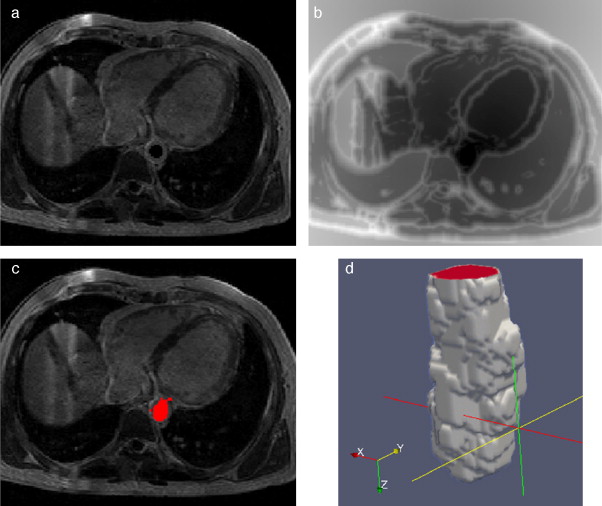

En la figura 15 se presentan los resultados obtenidos por cada etapa de procesamiento en IRM cardiovascular. Las imágenes médicas utilizadas tienen formato DICOM [39] , con 59 cortes de tamaño 192 × 192 pixels, voxel spacing: 1,5625 × 1,5625 × 2,5 mm . Por efectos de visualización, solamente se presenta uno de los cortes axiales de la imagen 3D.

|

Figura 15. Preproceso y segmentación el volumen del ventrículo izquierdo. (a) Corte axial de la IRM cardiovascular original. (b) Imagen (a) filtrada con difusión anisotrópica. (c) Imagen gradiente obtenida a partir de (b). (d) Imagen Watershed con segmentos etiquetados obtenida a partir de (c). (e) Selección del segmento del ventrículo izquierdo empleando umbralización. |